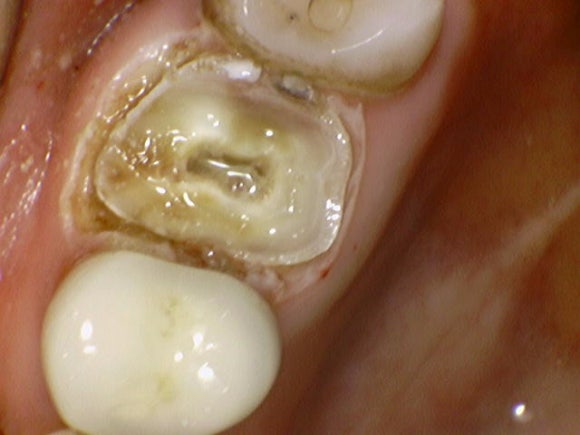

처참하게 부러진 치아입니다.

크라운째로 빠져서 오셨던 것 같습니다.

젊은 여자분이셨는데...

웃으면 보이는 보이는 위치에 치아가 없어져서 매우 당혹스러워하셨습니다.

난생처음 임플란트를 해야 한다는 두려움과 함께요.

충치가 뿌리까지 타고 내려갔는가?

저정도면 그렇다고 봐야겠죠.